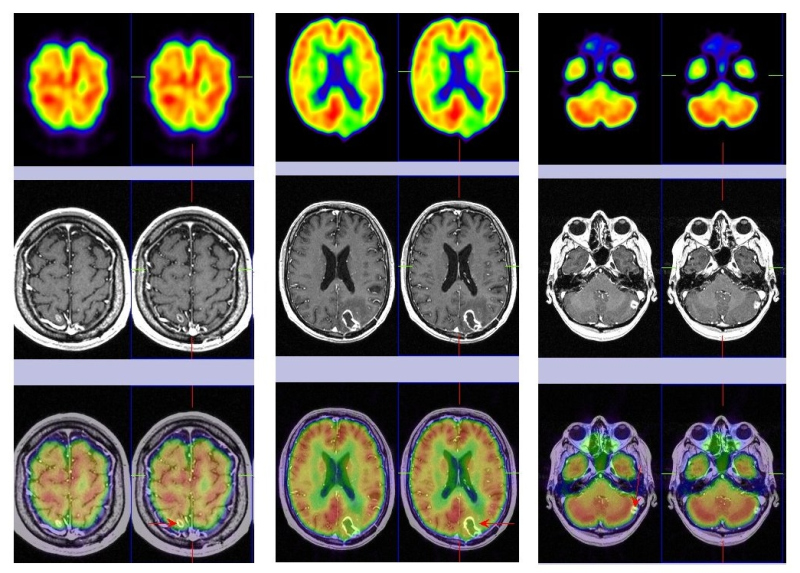

Al cabo de 3 meses refiere de nuevo deterioro neurológico presentando cefalea, inestabilidad en la marcha y acentuación de la hemiparesia izquierda. Se le realiza una RM cerebral de urgencia que muestra una cavidad porencefálica en lóbulo parietal derecho secundaria a cirugía, persiste la radionecrosis parieto-occipital izquierda y hay un incremento del tamaño de la lesión cerebelosa izquierda que se interpreta como recidiva tumoral. Tras el hallazgo de la RM se realiza nuevo estudio PET-RM de control (fig. 3) que detecta fijación patológica de la 18F-FDG en la lesión cerebelosa izquierda indicando recidiva tumoral maligna, ausencia de captación en lóbulo parietal derecho (cambios quirúrgicos) y en región parieto-occipital izquierda (radionecrosis). Ante dicha situación, se decide la extirpación quirúrgica de la metástasis cerebelosa izquierda y en la evolución se objetiva mejoría clínica.